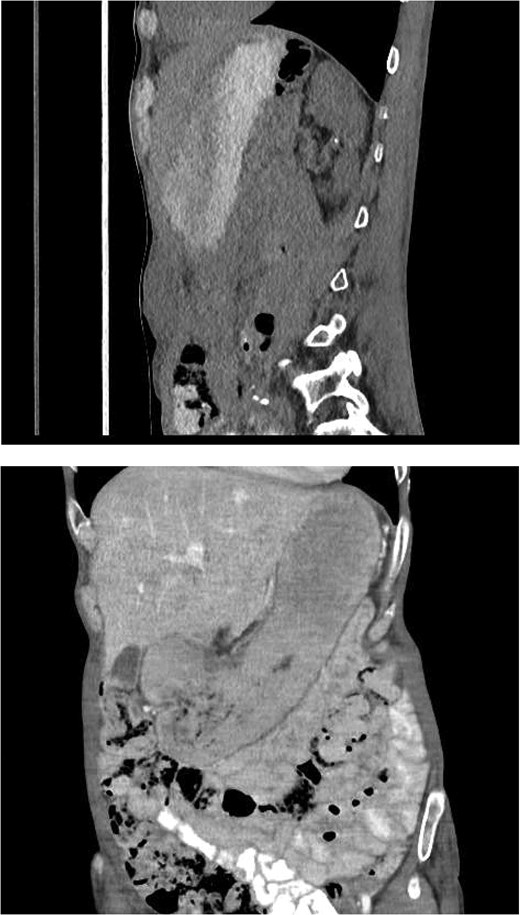

Repeated CT abdomen with oral contrast (Fig. 4): No oral contrast leak into the upper anterior abdominal fluid collection.

Repeated CT abdomen with oral contrast revealing no oral contrast leak into the upper anterior abdominal fluid collection.